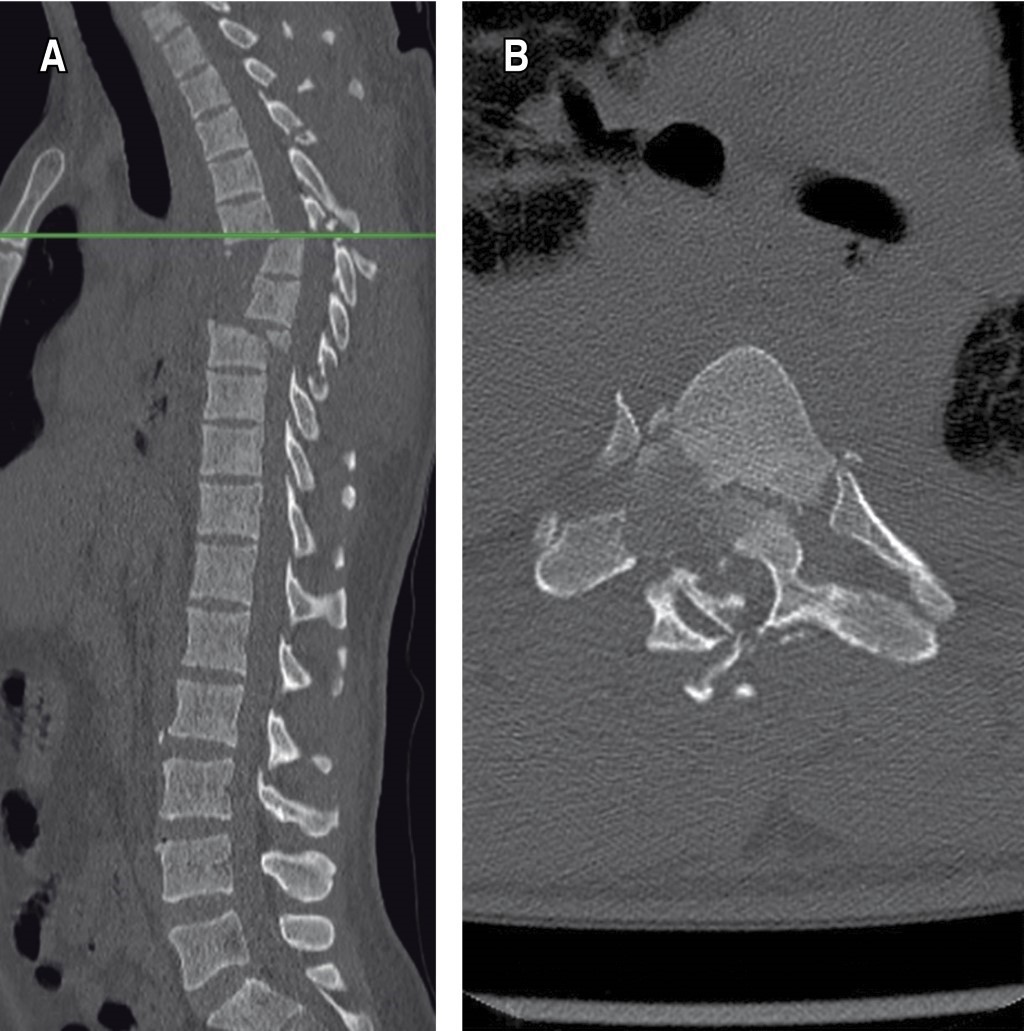

Figure 2